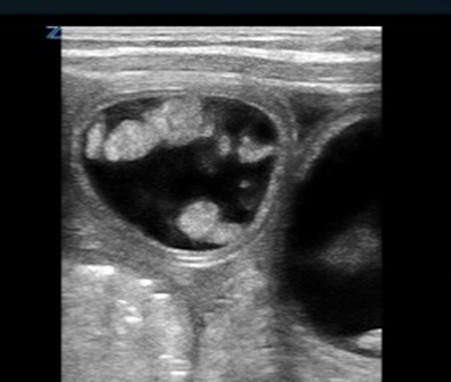

| Peritoneal fluid/Ascites | |

| Strengths | Considerations |

|

![]() |

Arrow indicates a septated peritoneal fluid collection |